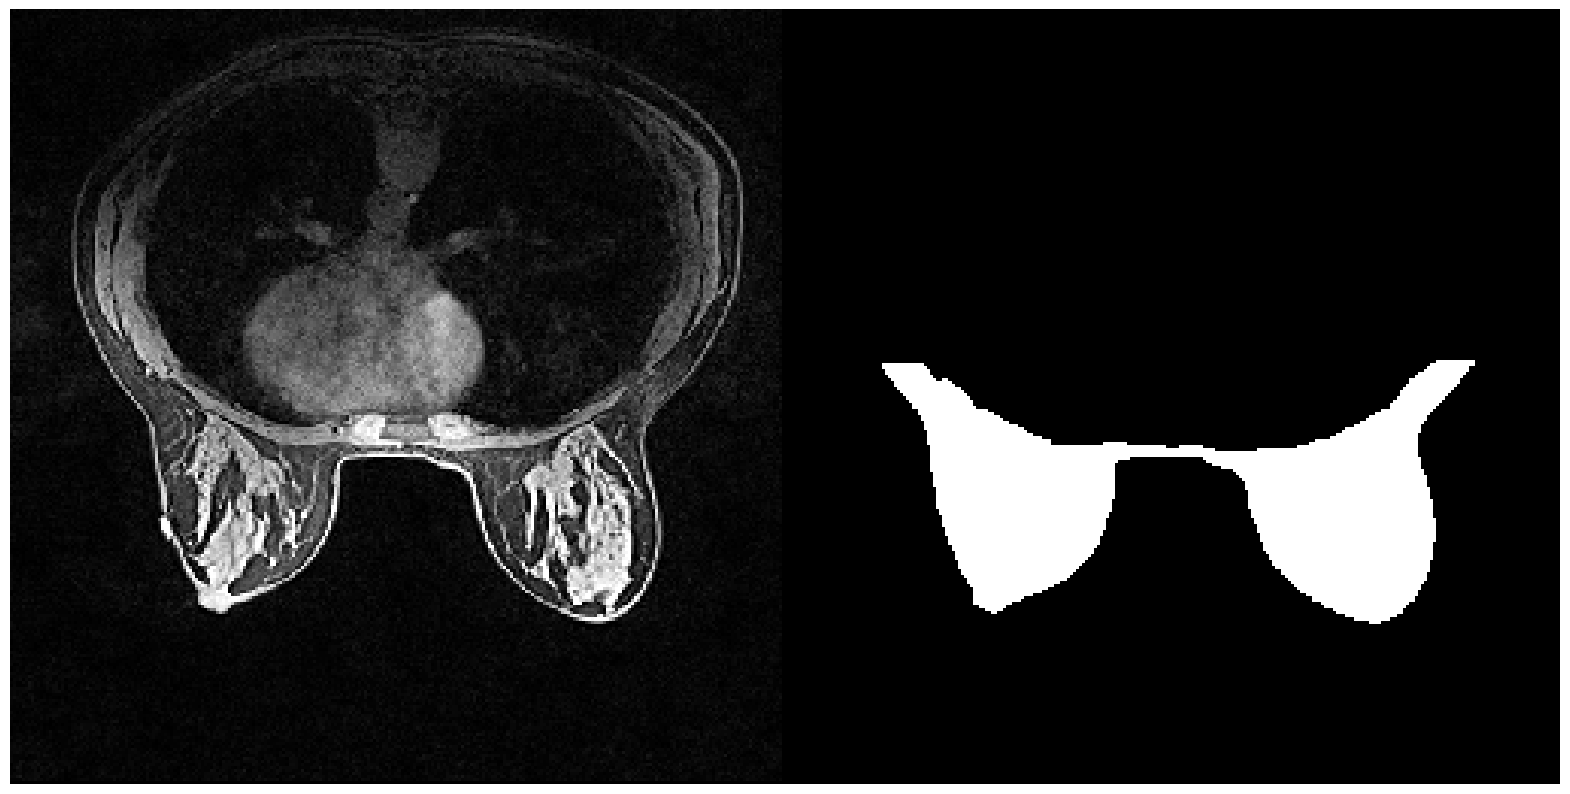

6.5.1 Validation with BFGT

The complete BFGT dataset contains 922 volumes of breast MRI images produced by GE and SIEMENS machines. We obtain 219 slices (up to 3 slices per volume) produced by the GE machine as our training and validation set. We then select 81 slices (up to 3 slices per volume) produced by SIEMENS as our out-of-domain dataset. Each image is resized to have the same dimension of 256×256256256256\times 256. We report below the mean IOUs and SBI of models trained on data with different augmentations.

Training set IOUvalsubscriptIOU𝑣𝑎𝑙\mbox{IOU}_{val} IOUnoisysubscriptIOU𝑛𝑜𝑖𝑠𝑦\mbox{IOU}_{noisy} IOUOODsubscriptIOU𝑂𝑂𝐷\mbox{IOU}_{OOD} SBI

No Augmentation 0.853 0.718 0.761 3.396

Color Jitter 0.830 0.744 0.820 3.726

NST 0.850 0.802 0.823 4.102

Sep. Color Jitter 0.872 0.730 0.780 3.696

Negative Insertion 0.867 0.717 0.748 3.996

Random Resized Crop 0.858 0.623 0.725 2.538

Random Crop Reflect 0.863 0.619 0.774 2.518

Table 4: Performance of models trained on datasets with different augmentations when applied to the validation set, dataset with noise injected, and dataset with naturally occurred domain shifts for BFGT

.

In experiments with BFGT, augmentations with no modifications on targets’ shapes achieved higher SBIs than the baseline model, while those that altered targets’ shapes resulted in models with smaller SBIs. This phenomenon matched our prediction. Color Jitter (brightness shifts for grayscale images), Sep. Color Jitter, and NST all lead to models with higher performance on OOD and Noisy data. In contrast, Negative Insertion showed no improvement in performance on OOD nor on Noisy data compared to the baseline, despite its higher SBI. This is because SBI also takes an SN’s performance on objects with dissimilar shapes into consideration. Random Resized Crop and Random Crop Reflect alter shape information in the training set. Both models have smaller SBIs than the baseline, plus similar or lower performance on OOD and noisy data. The results confirm that augmentation not altering shape improves models’ SBIs; Color Jitter and NST are apparently the most practical augmentation method to be applied to encourage shape learning and improve models’ generalizability.

Refer to caption

(a) Image from GE machine

(b) Image from SIEMENS machine

(c) The image collected from GE machine with (from left to right) Gaussian noise, shot noise, impulse noise, and defocus blur applied.

Figure 12: Samples from the three partitions of data domain in BFGT